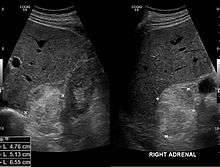

Most myelolipomas are unexpected findings on CT scans and MRI scans of the abdomen. They may sometimes be seen on a plain X-ray films.[6]